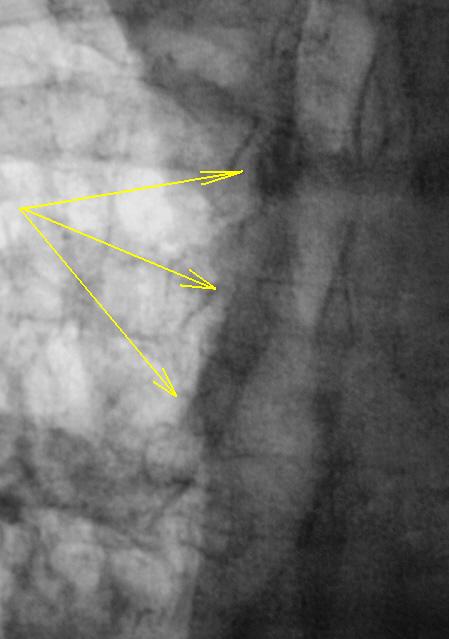

На следующем томографическом срезе четко дифференцируется "стелющееся объемное образование трахеи" с переходом на главный бронх и с распространением "опухолевого роста" за пределы стенки трахеи.

14.jpg